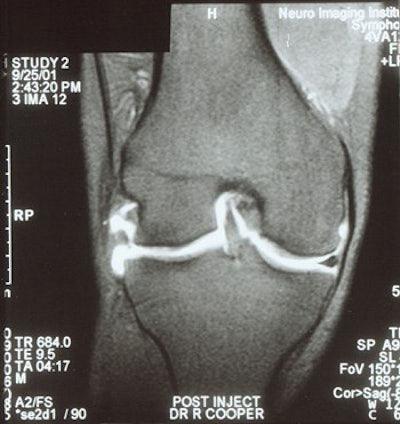

![]() |

| MR arthrogram demonstrates a meniscal re-tear in a patient with >25% meniscal resection. |